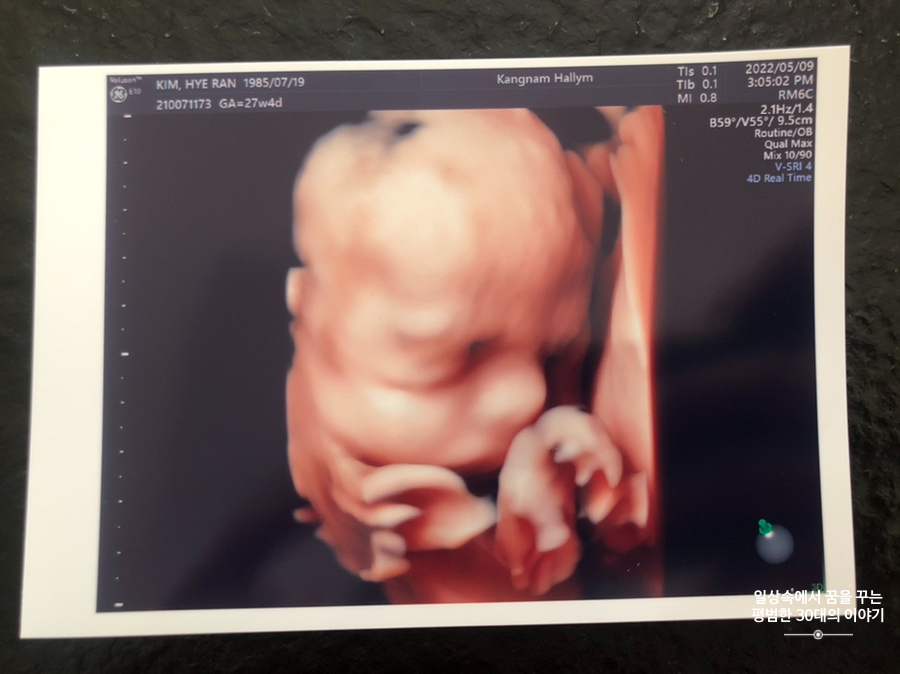

오늘은 입체 초음파 보는 날!!! 입체 초음파는 처음인데다 3주 만에 이안이 얼굴을 본다 생각하니 무척 설레는 마음으로 병원에 갔다. 첫 번째 시도에서는 계속 내 등 쪽으로 얼굴을 대고 엎드려 있어 실패! 초코우유 먹고 열심히 걸은 후, 30분 뒤에 다시 진행한 두 번째 시도에서는 얼굴 반쪽을 보여줬다. 얼굴 전면을 보지 못해 너무 아쉬웠지만 그래도 손가락 빨고 있는 모습, 웃고 있는 모습, 입 뻐끔 거리는 모습, 발차기 하는 모습, 손가락 쥐었다 폈다 하는 모습, 손을 휘적휘적 거리는 모습 등 다양한 모습을 보여줘서 그것만으로도 충분히 만족스러웠다. 내가 다니고 있는 강남성심병원은 입체 초음파가 다른 병원에 비해 무척 비싼 편인데(진료비 내역을 보니 초음파 진단료가 129800원 나옴) 그나마 위안을 삼을 수 있는 것은 화질이 그나마 좋은 편이라는 것이다.